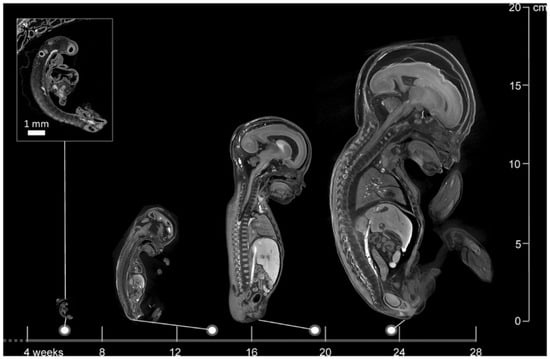

Miscarriage Tissue Research: Still in Its Infancy

by Rosa E. Lagerwerf, Laura Kox, Melek Rousian, Bernadette S. De Bakker and Yousif Dawood

Life 2026, 16(1), 128; https://doi.org/10.3390/life16010128 - 14 Jan 2026

Each year, around 23 million miscarriages occur worldwide, which have a substantial emotional impact on parents, and impose significant societal costs. While medical care accounts for most expenses, work productivity loss contributes significantly. Addressing underlying causes of miscarriage could improve parents’ mental health and potentially their economic impact. In most countries, investigations into miscarriage causes are only recommended after recurrent cases, focusing mainly on maternal factors. Fetal and placental tissue are rarely examined, as current guidelines do not advise routine genetic analyses of pregnancy tissue, because the impact of further clinical decision making and individual prognosis is unclear. However, this leaves over 90% of all miscarriage cases unexplained and highlights the need for alternative methods. We therefore conducted a narrative review on genetic analysis, autopsy, and imaging of products of conception (POC). Karyotyping, QF-PCR, SNP array, and aCGH were reviewed in different research settings, with QF-PCR being the most cost-effective, while obtaining the highest technical success rate. Karyotyping, historically being considered the gold standard for POC examination, was the least promising. Post-mortem imaging techniques including post-mortem ultrasound (PMUS), ultra-high-field magnetic resonance imaging (UHF-MRI), and microfocus computed tomography (micro-CT) show promising diagnostic capabilities in miscarriages, with micro-CT achieving the highest cost-effective performance. In conclusion, current guidelines do not recommend diagnostic testing for most cases, leaving the majority unexplained. Although genetic and imaging techniques show promising diagnostic potential, they should not yet be implemented in routine clinical care and require thorough evaluation within research settings—assessing not only diagnostic and psychosocial outcomes but also economic implications. Full article